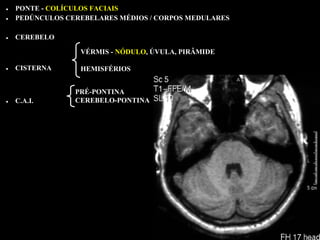

• PONTE - COLÍCULOS FACIAIS

• PEDÚNCULOS CEREBELARES MÉDIOS / CORPOS MEDULARES

• CEREBELO

VÉRMIS - NÓDULO, ÚVULA, PIRÂMIDE

• CISTERNA      HEMISFÉRIOS

PRÉ-PONTINA

• C.A.I.       CEREBELO-PONTINA